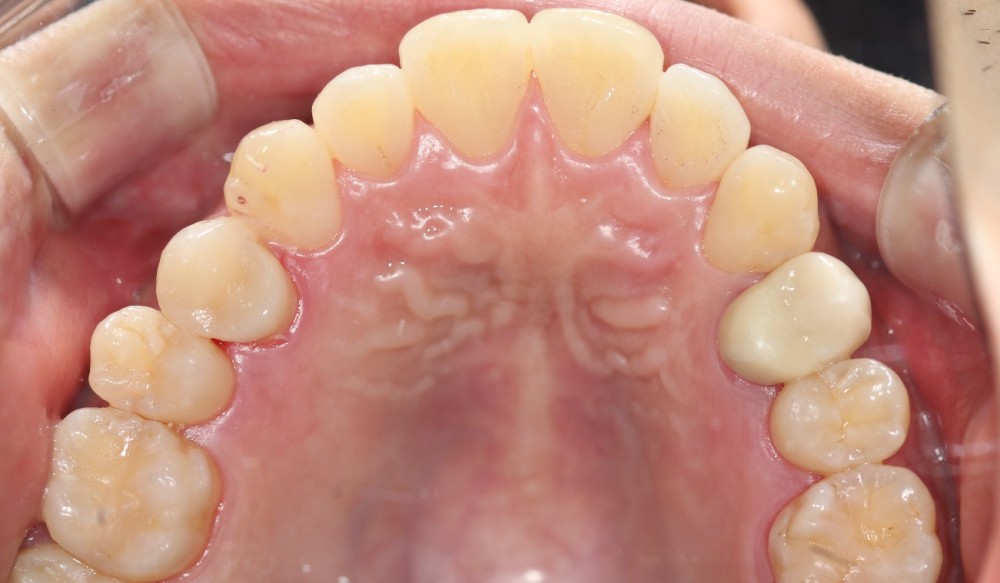

이맥스 인레이로 충치 치료하였습니다.

어느 치아가 치료한 치아일까요?

찾기 어려우시죠?

이처럼 이맥스 인레이는 아주 심미적이면서도 강도도 충분한 좋은 치료방법입니다.

저희 치과에서는 번거롭고 노력이 필요하지만 인레이 케이스는 정성을 다해 모두 이맥스로 치료합니다.